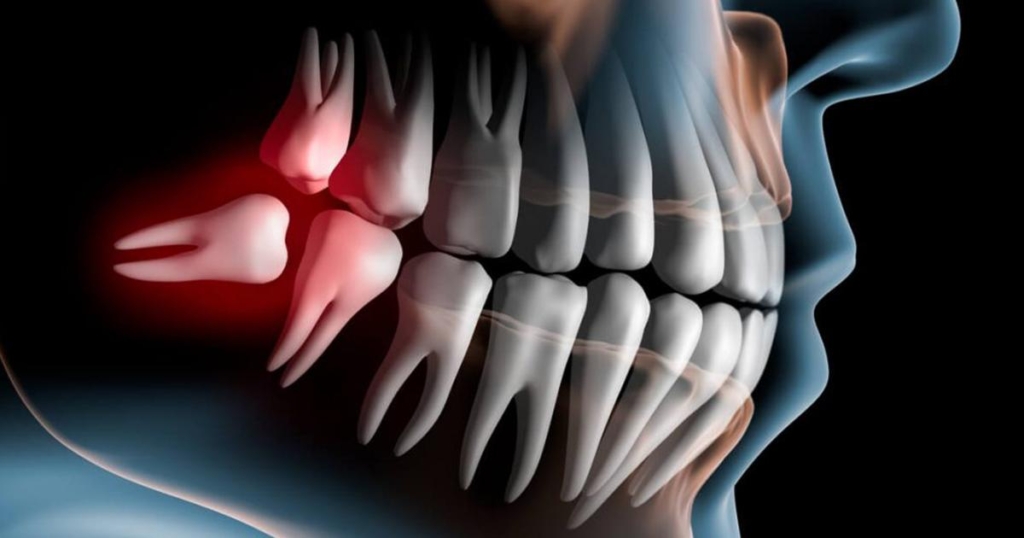

Sintomi della necessità di un'estrazione del dente

L’estrazione del dente viene eseguita quando:

- carie hanno distrutto o danneggiato la radice del dente;

- ha danneggiato la corona insieme a gran parte della radice;

- c’è un grave allentamento dei denti dovuto a malattia parodontale;

- il dente soffre di un’infiammazione che non può essere trattata in modo standard;

- il dente si trova su una mascella fratturata.